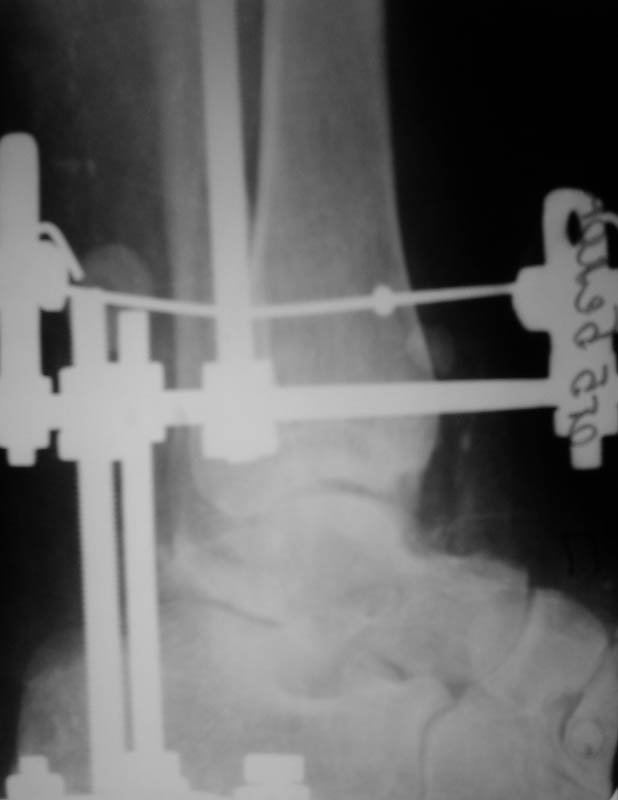

Диагноз: закрытый переломо-вывих таранной кости, двухлодыжечный перелом, подтаранный вывих стопы, асептические некрозы. Перелом был закрытый, но были некрозы из-за давления отломков (см.фото).

Что сделали. Под наркозом попытка закрытой ручной репозиции - безуспешно. Латеральный доступ, открытая репозиция таранной кости. Наложение АВФ (2 кольца, 2 полукольца на пятке и переднем отделе стопы). Устранение подтаранного вывиха стопы. Послеоперационные снимки в приложении.